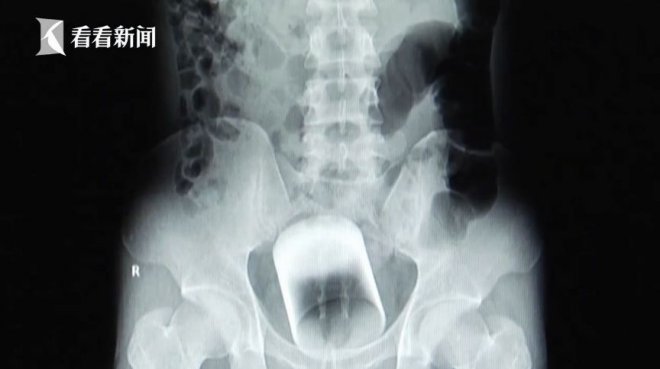

根據《TVBS》報導,委內瑞拉日前發生一起離奇的醫療個案,一名79歲老翁因為腹部下體劇烈疼痛就醫,當時曾無奈表示有3名搶劫犯闖入他家中,沒想到屋內沒有任何貴重物品,不滿空手而歸,便憤而將啤酒強硬塞入他的肛門裡,醫護人員一聽面面相覷,難以相信這是真的,不料照完X光,真的看到「完整酒瓶卡在肚子裡」的驚人畫面!

由於酒瓶卡住的位置過於深入,醫護人員幫他轉到10公里遠的中央醫院治療,緊急替他安排動手術,將其全身麻醉才能取出。據悉當時醫護人員也報了警,但老翁過往經驗已不止一次異物入體,曾有過自己玩得太開心,導致物品卡在體內的先例,目前未知當地警方是否有展開調查,只能說如果是自己來的話,還是要適可而止才好啊!

看到X光畫面真的太驚人了......一不小心就會出大事啊!